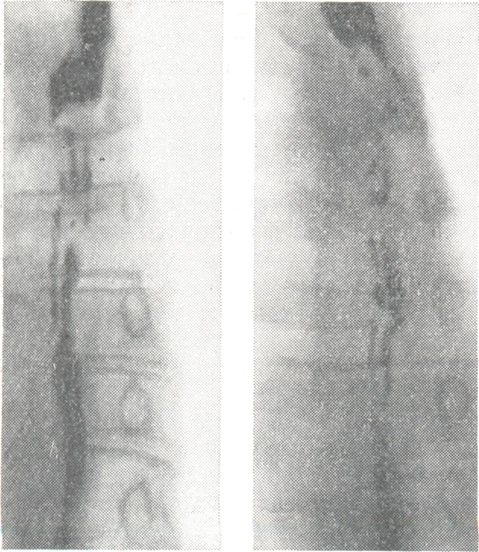

Диагностика возможна лишь с помощью контрастного рентгенологического исследования, при к-ром определяется характерный четкообразный вид пищевода. Участки пищевода, расположенные между двумя соседними спастически сокращенными отрезками, могут иметь округлую, овоидную или неправильную косую форму. Нередко можно наблюдать спонтанное расправление спазмированных участков пищевода или перемещение их в каудальном направлении; в других случаях рентгеновская картина длительное время остается стабильной.

Применение атропина, папаверина, метацина, нитритов приводит к временному ослаблению или исчезновению спазмов и восстановлению проходимости пищевода. Изменчивость рентгенологической картины (рис.), а также реакция на указанные препараты позволяют правильно провести дифференциальную диагностику. В трудных для диагностики случаях может быть применена париетография пищевода (см. Париетография).